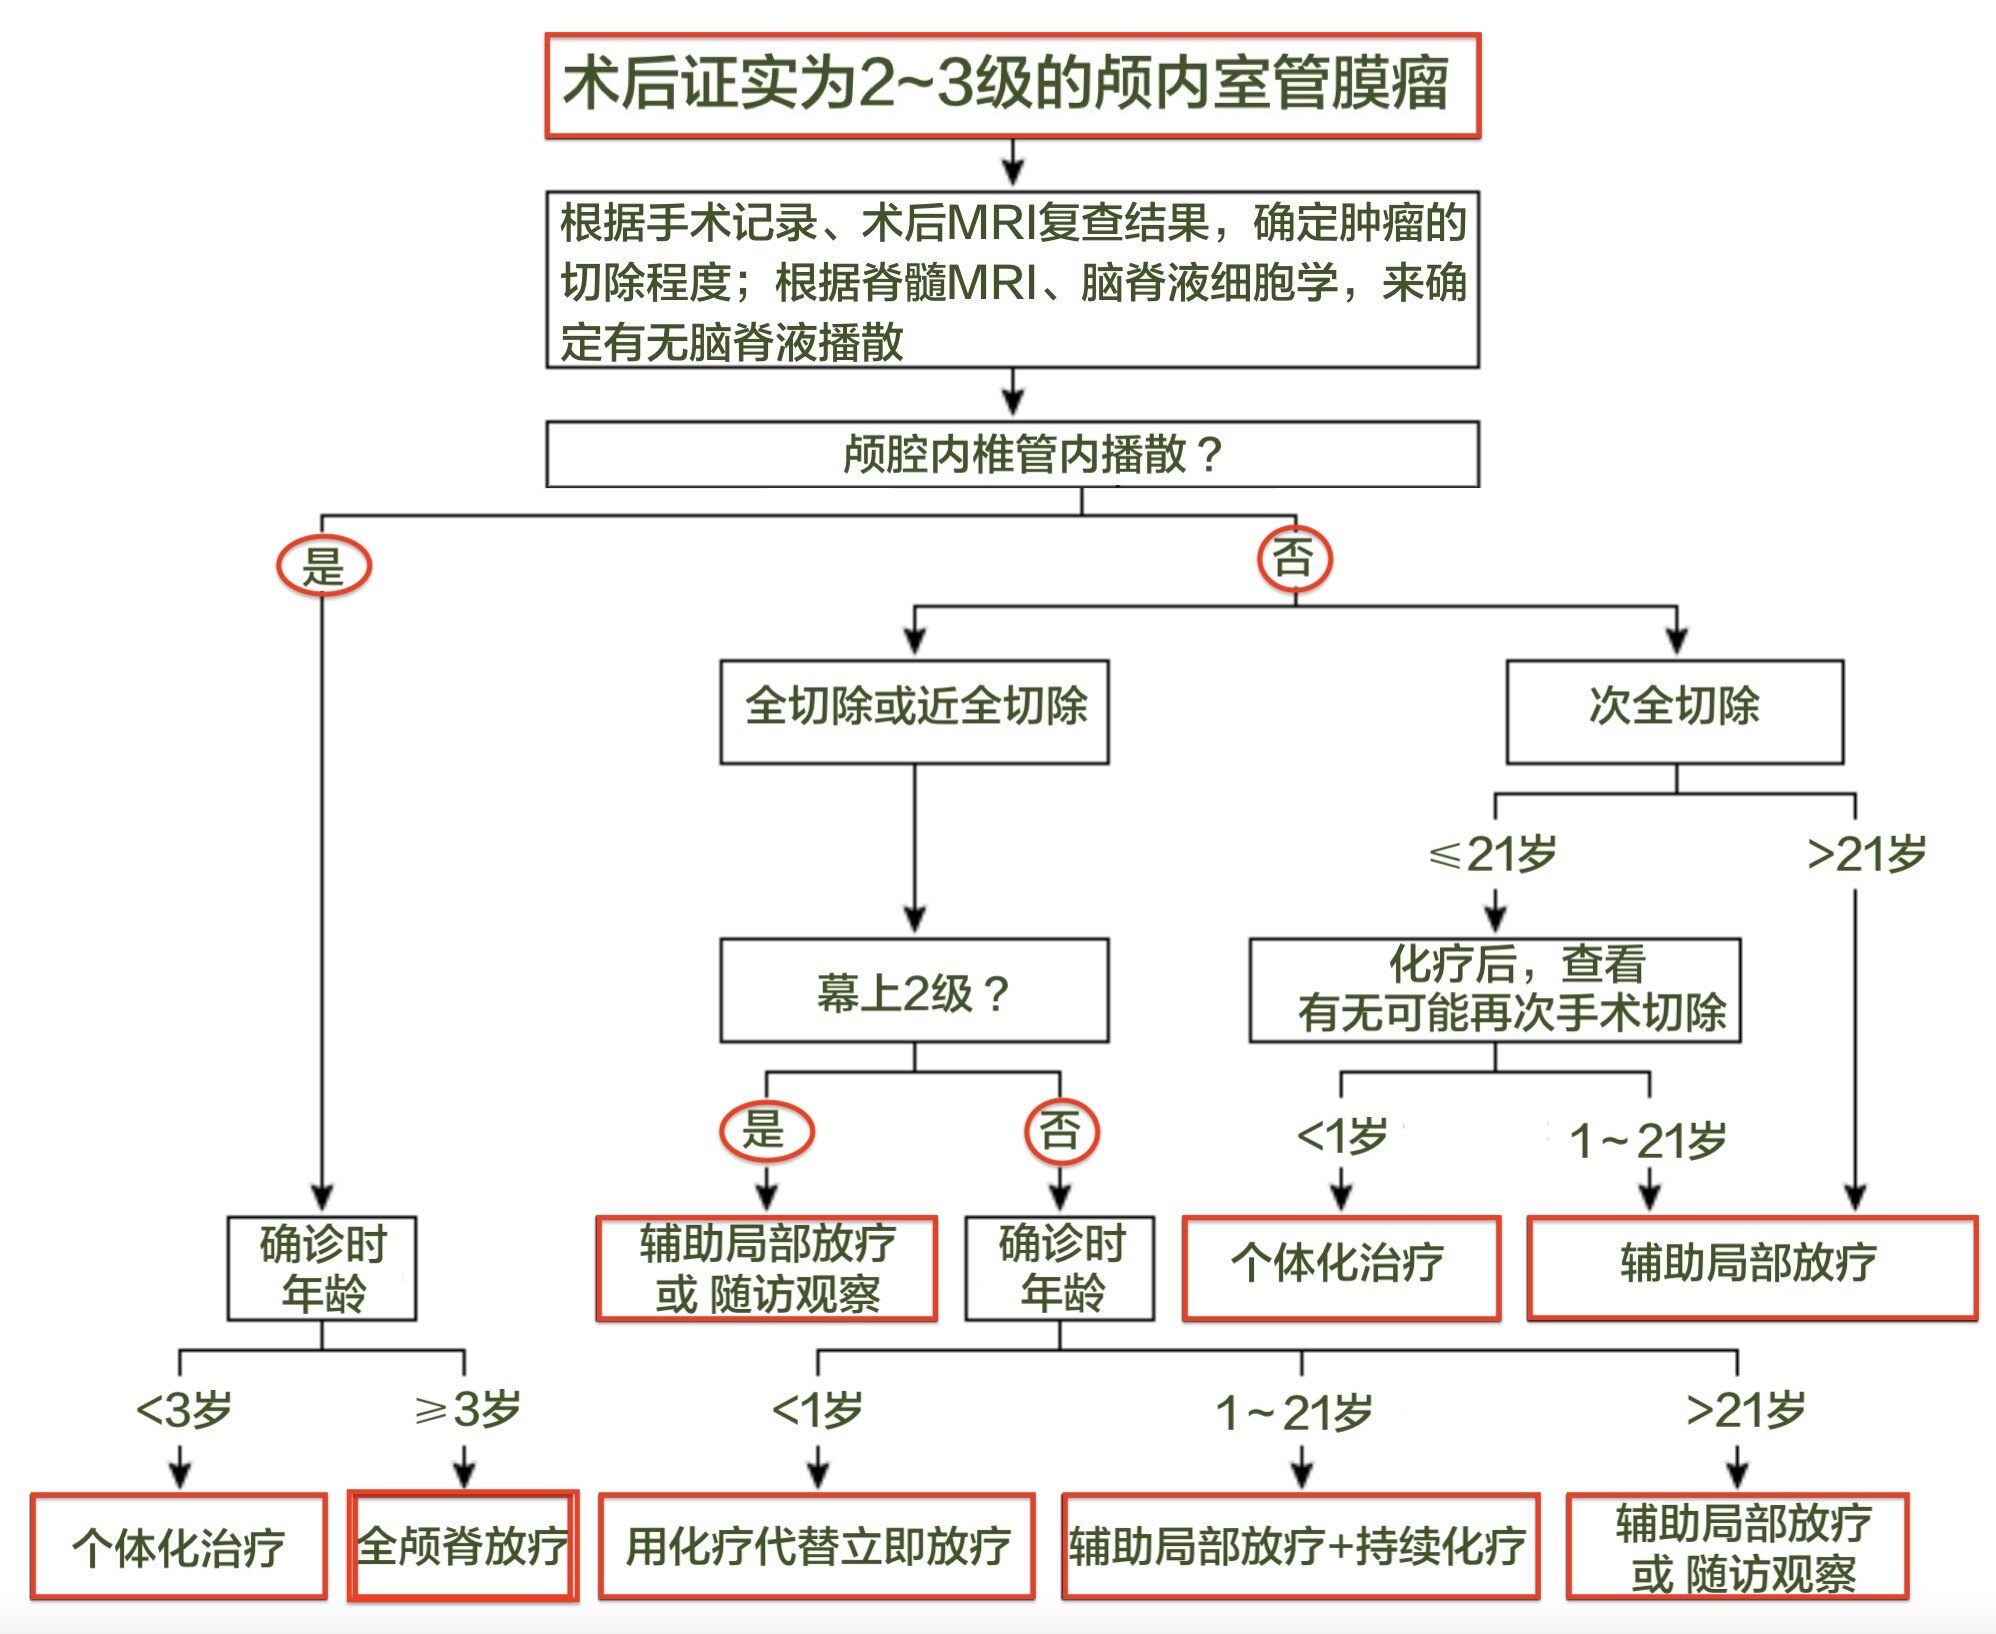

在获得更好的分子预后标志物之前,目前的治疗方法仍着重于将肿瘤切除程度视为辅助治疗的主要决定因素。

任何级别的室管膜瘤,在全切除后都应直接接受适形放疗,除非患者参加经审批的前瞻性临床试验或者年龄非常小(例如<1岁)。

接受全切的患者

大多数Ⅱ级和Ⅲ级颅内室管膜瘤患者在全切或近全切除后的标准治疗为术后放疗,以降低局部复发风险。

主要的例外如下:

①年龄极小的儿童(<1岁),通常可给予化疗以尽量避免放疗对发育的潜在不良影响;以及

②Ⅱ级幕上室管膜瘤全切的患者,这类患者预后良好可考虑观察处理而不是术后立即放疗。

接受次全切除的患者的无进展生存期和总生存期总是更差。建议这些高风险患者在术后接受短期化疗,若条件允许可行二次探查手术,然后再予以适形放疗。

患者通常在术后接受1~4个周期的多药化疗,然后复行MRI检查确定有无残余肿瘤,若有残余肿瘤则评估能否安全切除。有可能切除残余肿瘤的患者可先接受二次减瘤手术,再行辅助局部放疗。

小于1岁的患儿

建议采用辅助化疗作为推迟辅助放疗的过渡措施。

化疗后仍有残余肿瘤的患儿可考虑接受二次探查手术,这些患儿应尽可能在三级专科医疗中心接受治疗。

在1岁以上患儿中,局部放疗对局部控制和长期生存的潜在益处通常大于风险。